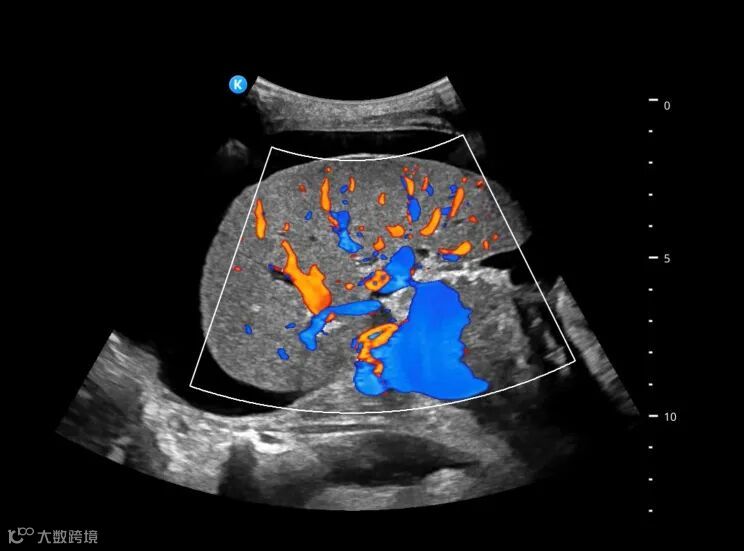

深圳鲲为科技有限公司是以突破性原创技术引领,并致力于下一代超分辨超声开发的专业影像设备公司。